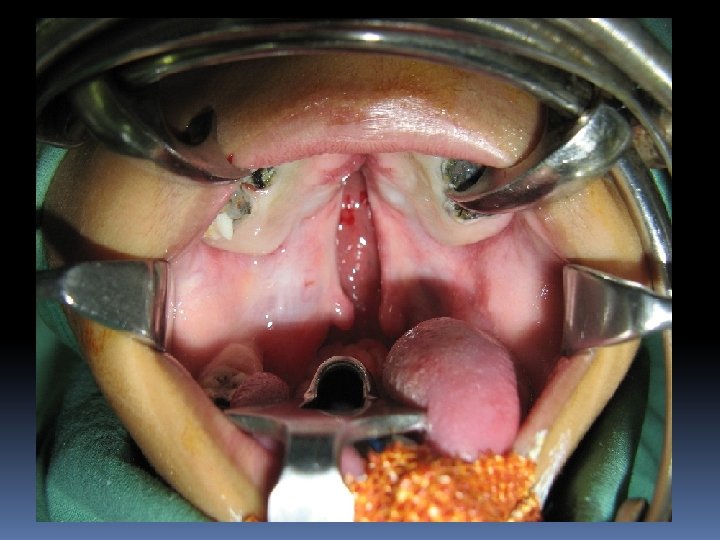

Case Baby X a case of APERT SYNDROME with Incomplete cleft palate was posted for palatorplasty.

Anaesthetic Management IV line secured with difficulty Pre oxygenation done Inhalation induction : 6% Sevoflurane+ N 2 O + O 2 Trial laryngoscopy done, epiglottis visualised Induced with PROPOFOL 45 mg, FENTANYL 25 mic Orally intubated with 5 size uncuffed RAE tube Maintenance N 2 O + O 2 + Atracurium + Sevo Intraop – uneventful baby Girl extubated on table, smooth postop